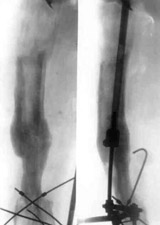

Results of treatment.Results of treatment.

Results of treatment.